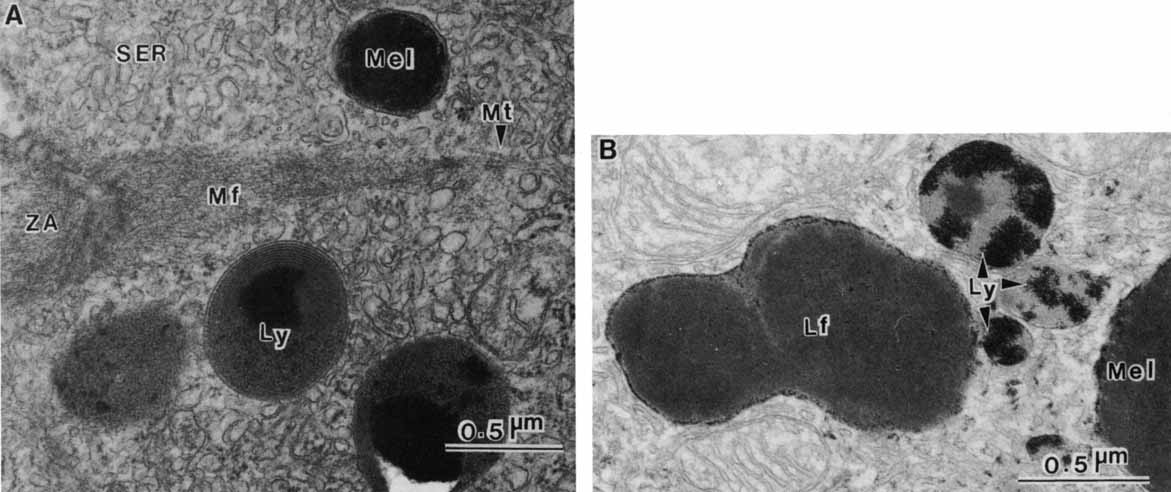

pigmentation. Pigment Cell Res 12:219–236, 1999 65. Schraermeyer U, Peters S, Thumann G, Mociok N, Heiman K: Melanin granules of the retinal pigment epithelium are connected with the

lysosomal degradation pathway. Exp Eye Res 68:237–245, 1999 66. Eldred GE: Lipofuchsin and other lysosomal storage deposits in the retinal pigment

epithelium. In Marmor MF, Wolfensberger TJ, (eds): The Retinal Pigment Epithelium. New York: Oxford University Press, 1998:651–668 67. Feeney-Burns L, Hilderbrand ES, Eldridge S: Aging human RPE: Morphometric analysis of macular, equatorial, and peripheral